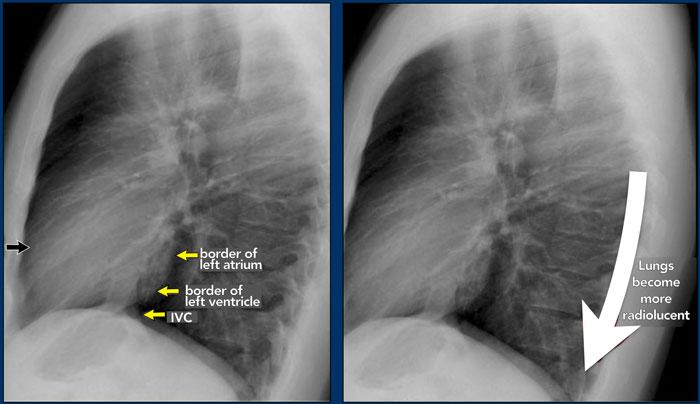

Trên phim X-quang ngực tư thế nghiêng, các bờ tim cần được xác định rõ ràng, và tĩnh mạch chủ dưới (IVC) thường có thể thấy đổ vào nhĩ phải.

Khoang sáng sau xương ức

Khoang sau xương ức bình thường chứa phổi có khí và do đó phải có hình ảnh thấu quang (tối trên phim), kéo dài xuống dưới đến mức thất phải tiếp xúc với xương ức (mũi tên đen nhỏ).

Bất kỳ hình mờ nào trong khoang sau xương ức phía trên đều đáng ngờ về tổn thương trung thất trước hoặc khối xuất phát từ các thùy trên của phổi.

Dấu hiệu cột sống

Khi đánh giá các thân đốt sống trên tư thế nghiêng, chúng phải có hình ảnh thấu quang (tối hơn) tăng dần từ trên xuống dưới do lượng phổi có khí chồng lên ngày càng nhiều (mũi tên trắng).

Nếu các đốt sống ngực dưới có hình ảnh đậm bất thường, điều này có thể gợi ý bệnh lý ở các thùy dưới, chẳng hạn như đông đặc hoặc khối — đây được gọi là dấu hiệu cột sống.

Đánh giá Cơ hoành

- Vòm hoành phải phải được nhìn thấy rõ ràng ở phía trước đến tận thành ngực (mũi tên đỏ), thể hiện ranh giới giữa phổi có khí và mô mềm ổ bụng.

- Vòm hoành trái thường chỉ nhìn thấy đến điểm tiếp giáp với bóng tim (mũi tên xanh lam), phía ngoài điểm đó ranh giới bị mất do tỷ trọng tương đương giữa tim và các tạng bụng phía trên.